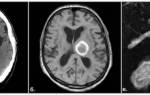

• Бесконтрастная компьютерная томография (КТ) — надежный метод диагностики острых гематом головного мозга. КТ позволяет выявить гематому, её объём и влияние на структуры мозга. На основе КТ-снимков нейрохирург определяет тактику и объём операции. Большинство стационаров, особенно экстренной помощи, оснащены КТ-аппаратами. Однако в хронической стадии и при сосудистых пороках без кровоизлияния КТ может быть недостаточно информативной. В таких случаях используют МРТ.

• Магнитно-резонансная томография (МРТ) позволяет более детально изучить мягкотканные структуры. Если диагностика затруднена после КТ, врач может назначить МРТ.

В диагностике клинической значимости нейровизуализация играет важную роль. Первоначально для исследования головного мозга назначают компьютерную томографию (КТ). Этот недорогой метод позволяет быстро определить наличие крови в веществе головного мозга, а также расположение и объем сгустка. Информативность КТ достигает максимума через 2-3 недели после появления гематомы (максимум 5 недель). В этот период участок внутримозговой гематомы (ВМГ) имеет повышенную плотность, что облегчает диагностику, и можно ограничиться одной КТ.

С течением времени (в среднем через 14-21 день) плотность геморрагической массы уменьшается, она становится изоплотной, то есть приближается к нормальным мозговым тканям. В этот период и позже качественную информацию о внутримозговой гематоме и состоянии мозга может предоставить магнитно-резонансная томография (МРТ).